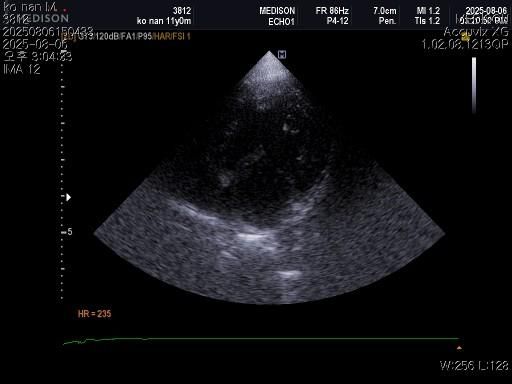

강아지 혈뇨의 원인을 찾고 있습니다 저희 강아지 두번도 아니고 딱 한번만 살려주세요..

1) 혈액검사와 엑스레이 그리고 초음파상 혈뇨의 원인이 나타나지가 않는지 궁금합니다.